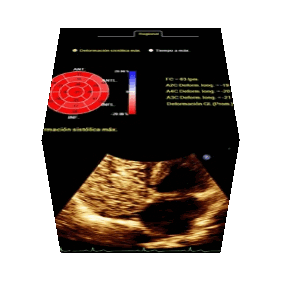

Ecocardiograma

Consiste en la realización de un ultrasonido del corazón con el cual el médico especialista puede determinar el tamaño de las cavidades cardíacas el movimiento de las paredes del corazón la función de las válvulas cardiacas y puede diagnosticar algunas enfermedades cardiacas que no se pueden diagnosticar por otro método